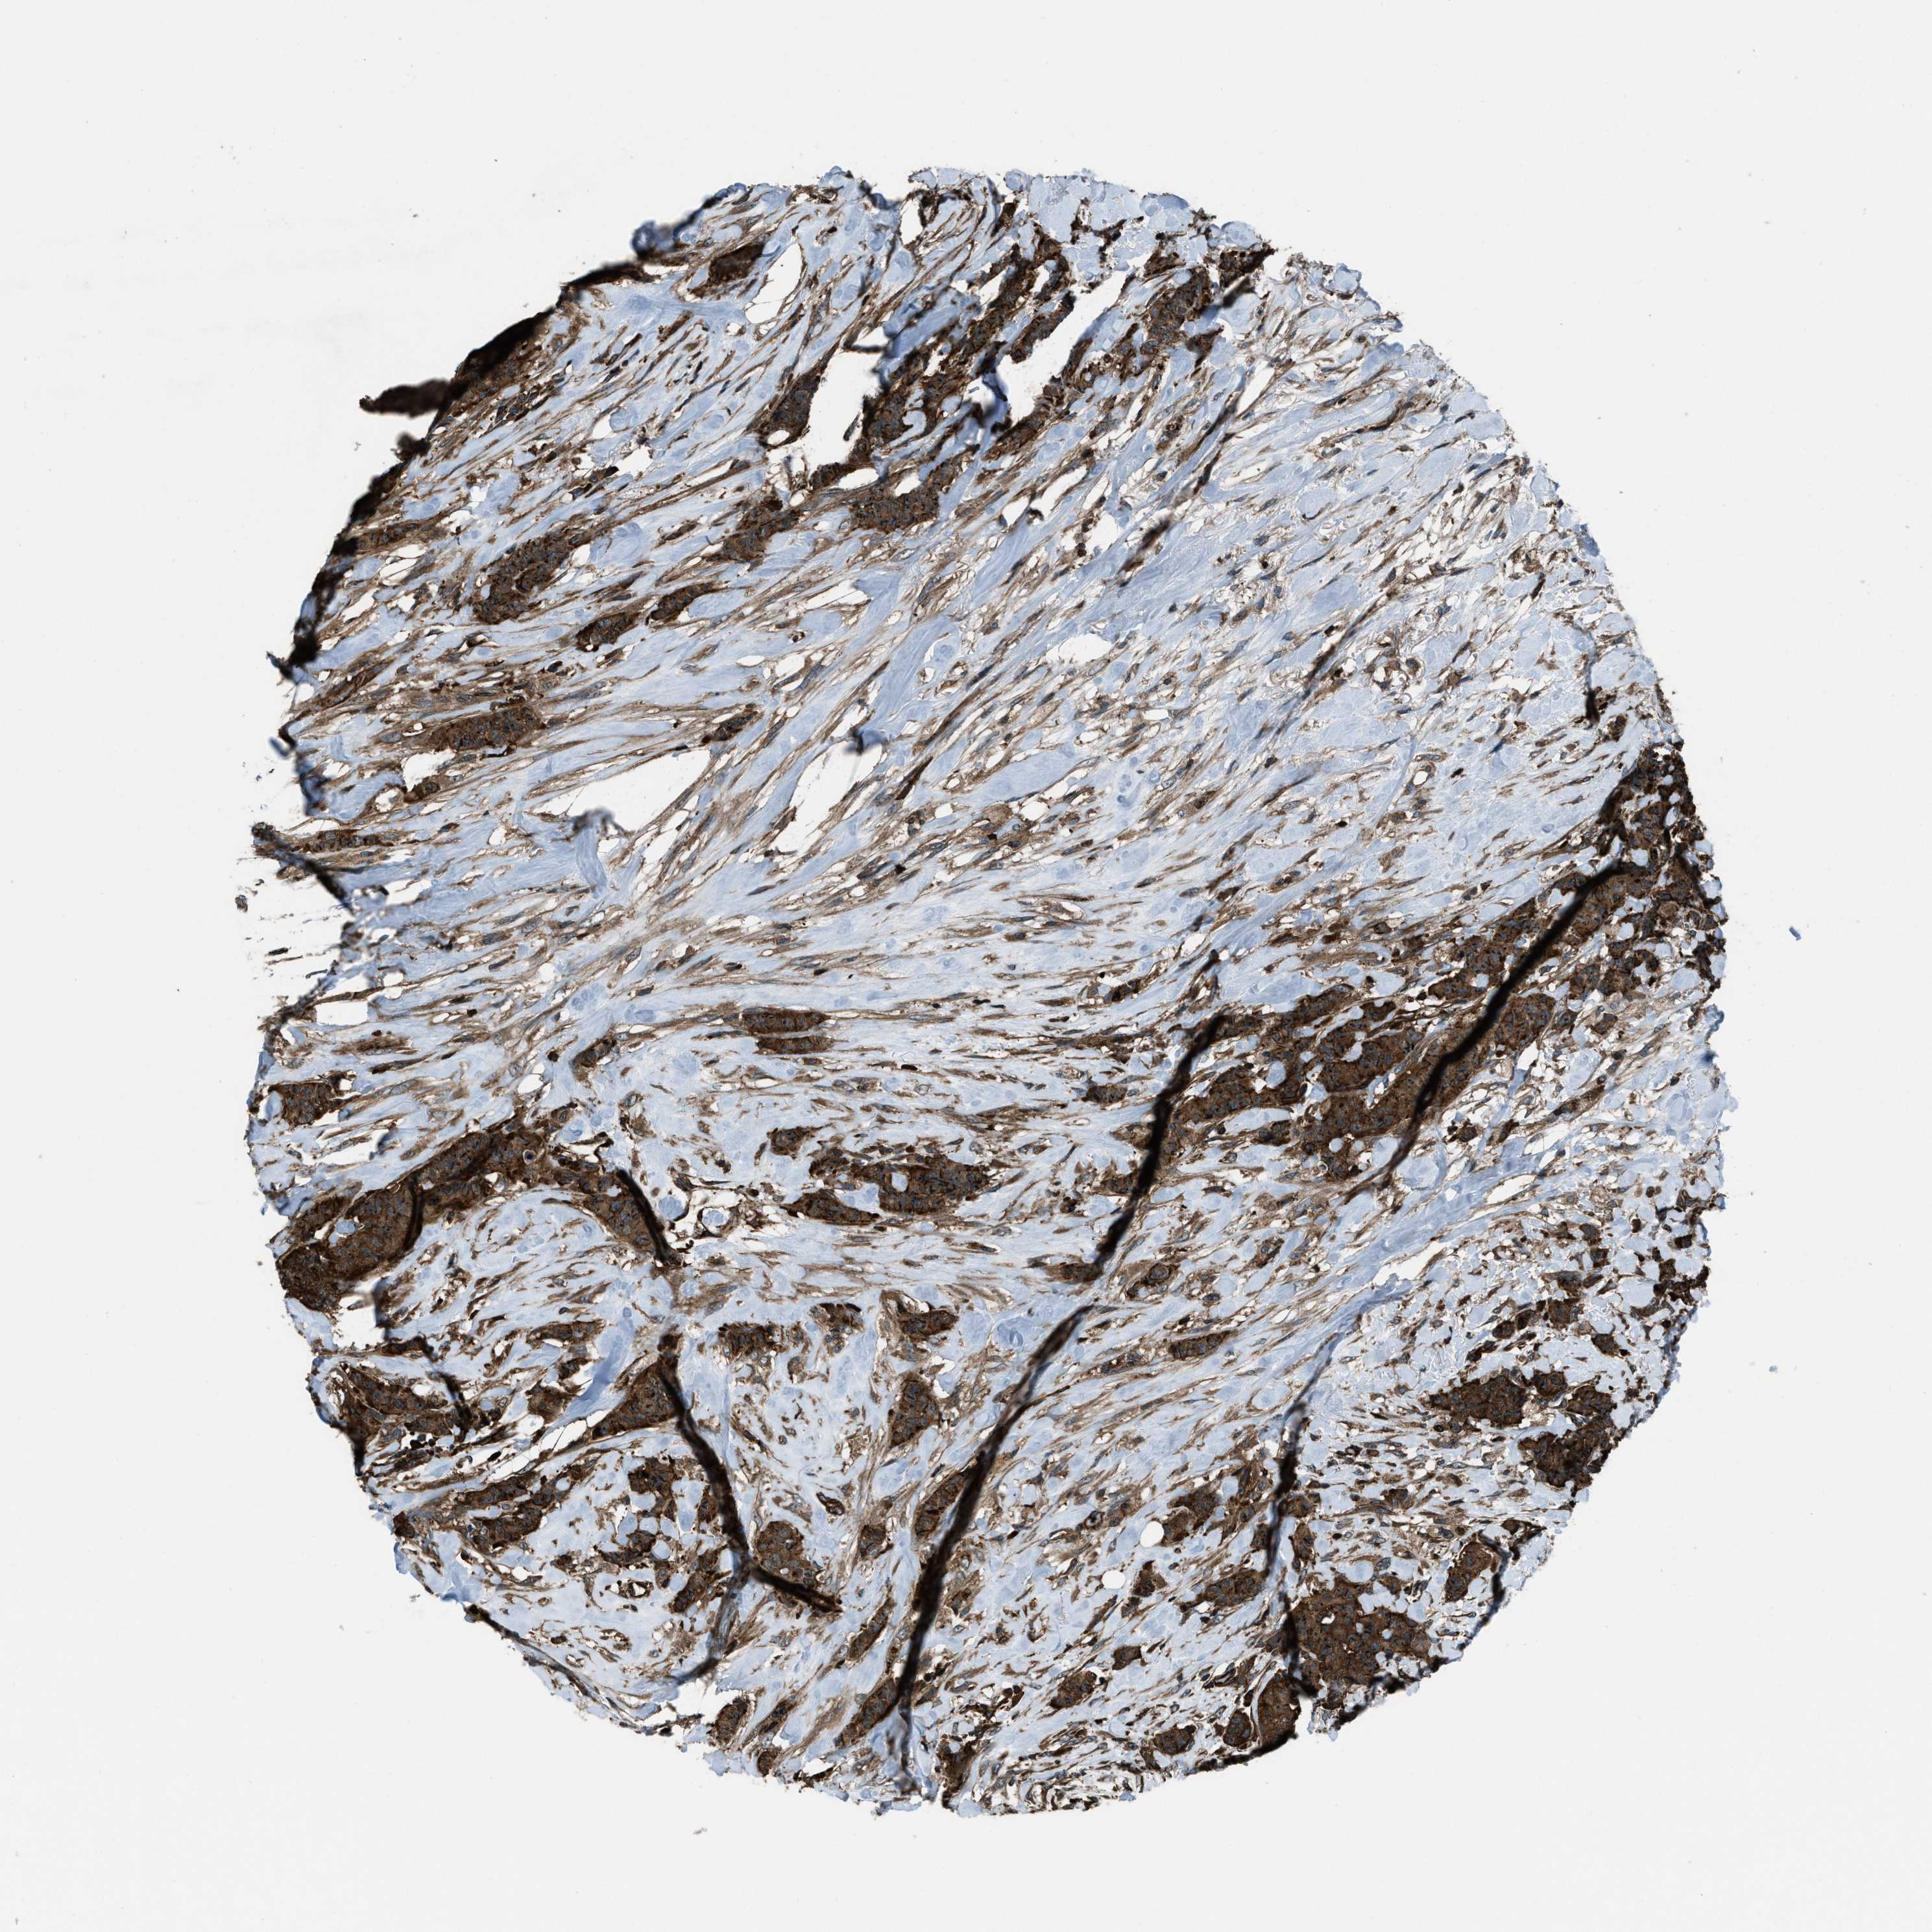

CANCER BREAST CANCER Show tissue menu

BRCA TCGA BRCA VALIDATION PROTEIN EXPRESSION